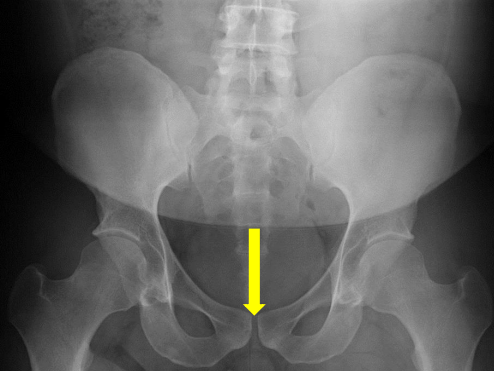

Femur heads

Ischial tuberosities

Pubic symphysis